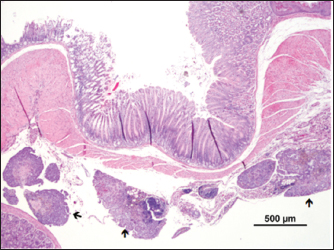

Fig. 7. Metastasis on gut serosa ( ) (H&E).

The mass presented areas of epidermal differentiation with laminated keratin and sebaceous glands. Cell differentiation into digestive and respiratory epithelium, bone, cartilage, and vast areas of differentiation into nervous tissue were also present (Figs. 37). Moreover, the nervous tissue presented focal areas of ependymoma. Epithelial areas with hypercellularity, cell atypia, stromal microinvasion, hemorrhages, and necrosis were also observed. Metastatic epithelial cells were detected invading the pancreas, the small intestine serosa, and the mesenterium. Therefore, the mass was classified as a malignant teratoma with abdominal carcinomatosis.

Although some reports of spontaneous ovarian teratomas in several strains of laboratory mice have appeared in the literature over the years, no reports were found in FVB/n mice. In the present case, for the first time, an ovarian teratoma was identified in a female laboratory FVB/n mouse, consisting of tissues originating from the three embryonic layers (endoderm, mesoderm, and ectoderm). The presence of invasive neoplasia and peritoneal carcinomatosis lesions confirms its malignant character. Though metastasis is rare, intra-abdominal metastasis was also reported to be associated with immature cat teratomas (Sirivisoot et al., 2022).